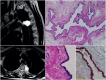

The diagnosis of a mediastinal mass may be challenging for clinicians, since lesions arising within the mediastinum include a variety of disease entities, frequently requiring a multidisciplinary approach. Age and sex represent important information, which need to be integrated with imaging and laboratory findings. In addition, the location of the mediastinal lesion is fundamental; indeed, we propose to illustrate mediastinal diseases based on the compartment of origin. We consider that this structured approach may serve as hint to the diagnostic modalities and management of mediastinal diseases. In this review, we present primary mediastinal tumours in the evolving context of new diagnostic and therapeutic tools, with recently described entities, based on our own experience with >900 cases encountered in the past 10 years.